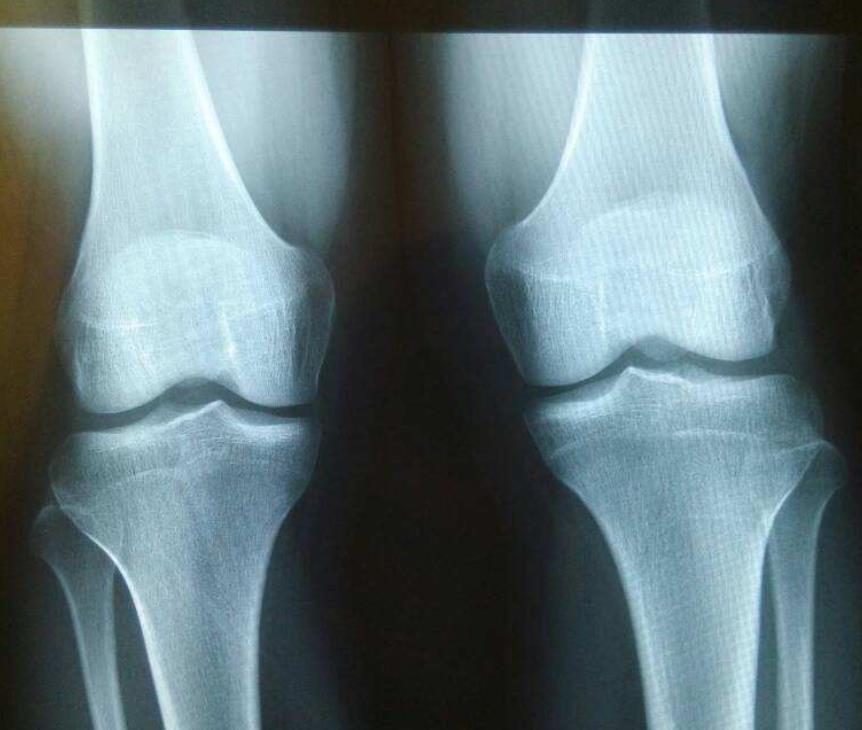

对于父母所说的以后会长高,李亚诺一开始也是深信不疑的,但是在一次医院的检查之后,医生告诉他:“你的骨垢线已经闭合了,以后基本上是不可能再通过自然发育的方式长高了。”

骨垢线

这个消息对于李亚诺来说就如同晴天霹雳额一般,他怎么也不敢相信医生所说的话,但是拍出来的CT不会骗人,李亚诺只能无可奈何地接受这个现实,最后失魂落魄的从医院里走了出来。

手术室中,医生为李亚诺进行了麻醉,然后就是长达六个小时的手术过程,切断双腿的骨头之后,医生用牵引器连接了大腿骨,这样之后可以每天保证骨头能够愈合一毫米,只要等骨头完全愈合之后再把牵引器取出就大功告成了。